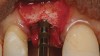

A long diamond bur was used to make a cut, which was 6-mm to 8-mm deep in the center of the alveolar ridge (Figure 3). The cut was made at least 1 mm away from the adjacent teeth in order to prevent any damage to them. A 4-mm wide bone-spreading chisel was used to mobilize and displace the buccal plate facially (Figure 4) so that a small, tapered osteotome for expansion could be used for implant site preparations. A 2-mm round bur was used to mark the implant location, and a 2-mm twist drill was used to guide the expansion with osteotomes.

Tapered osteotomes were used to expand the ridge completely to the working length, which was at least 10 mm (Figure 5). It should be noted that if too much resistance is encountered, a drill smaller in diameter than a previously used osteotome can be used along the palatal wall. An implant was then placed into the osteotomy created by tapered osteotomes (Figure 6). Minor cracks were found in the middle of the expanded buccal plate during and after implant placement. Particulate bone allograft (freeze-dried bone allograft) was used to fill the gap between buccal and palatal alveolar plates, and another bone graft (bovine bone mineral) was packed outside the expanded buccal plate. A resorbable membrane was placed over the buccal plate and bone grafts (Figure 7 and Figure 8).